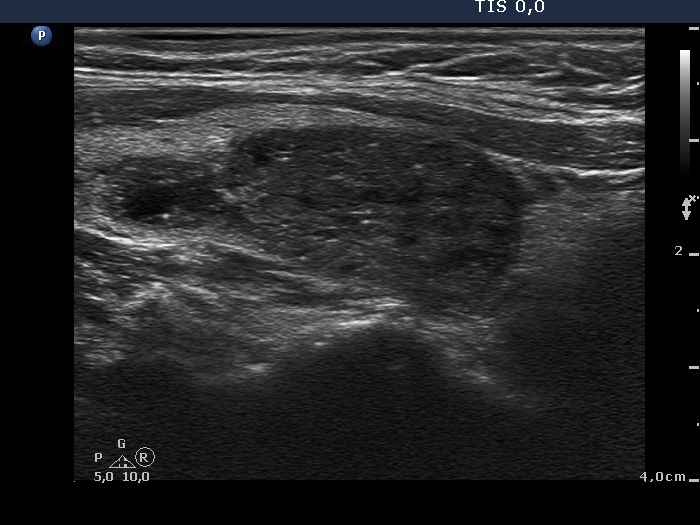

Granulation around surgical thread (histological diagnosis) - case 411 |

Papillary carcinoma (histological diagnosis) - case 779 |

Here is another example of the differential diagnostic problem caused by granulation around surgical thread. Again, there is no difference between the ultrasound presentations of these cases except for the vascularization. The right, malignant case cannot be a granulation around surgical thread which is always avascular; however, this is not a great revelation in a patient who has not been operated. Conversely, the lack of vascularization by no means excludes the possibility of a carcinoma.